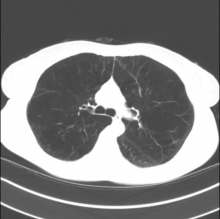

A 50-year-old woman with severe emphysema due to smoking underwent lung volume reduction surgery of her right upper lobe.

Patients are mobilized on the day of their surgery and should be prepared for discharge within 2-5 days, though sometimes recovery takes longer. Patients may go home with their chest drains still inserted. This patient left the hospital after three days with her chest drain removed, displaying an excellent clinical response. Three months later, the residual volume had reduced by 1.1 L and exercise distance was increased 70%. The St George’s Respiratory Questionnaire score had improved significantly, and the patient was keen for contralateral surgery.